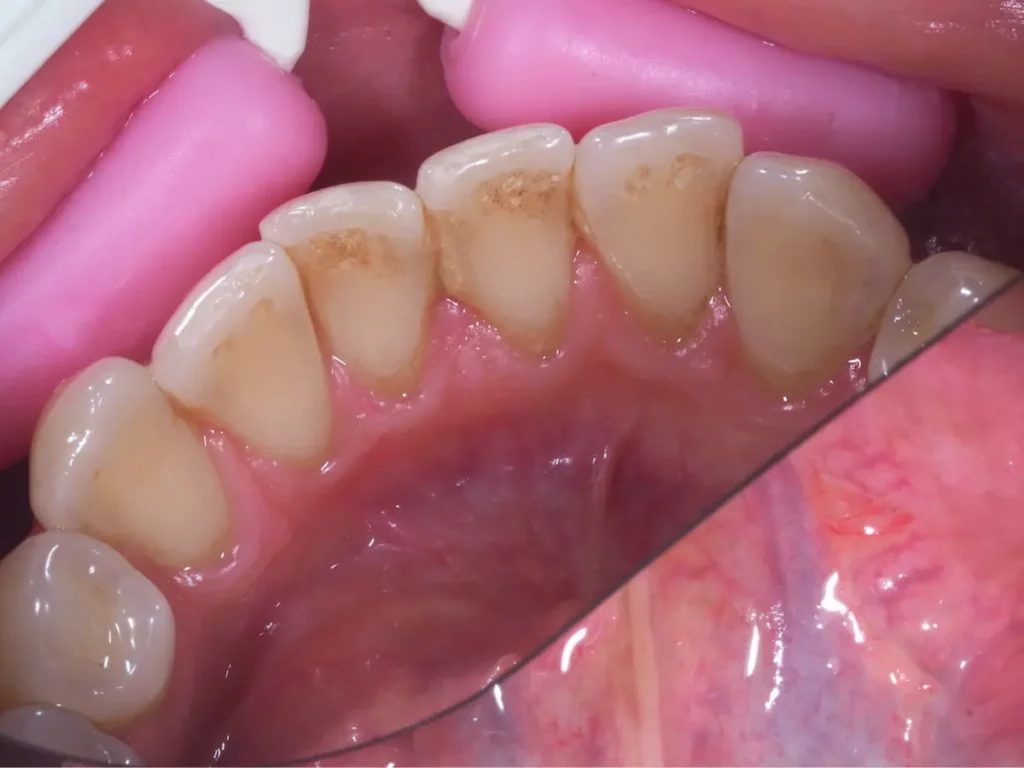

Zbliżenie dolnych zębów z brązowym osadem przy linii dziąseł przed zabiegiem higienizacji

Kamień nazębny gromadzi się głównie w miejscach, gdzie osad nazębny odkłada się w największych ilościach, takich jak przy linii dziąseł, w obrębie jamy ustnej. Proces ten jest przyspieszany przez nieodpowiednią higienę jamy ustnej, co może prowadzić do poważniejszych problemów zdrowotnych, takich jak zapalenie dziąseł i choroby przyzębia.